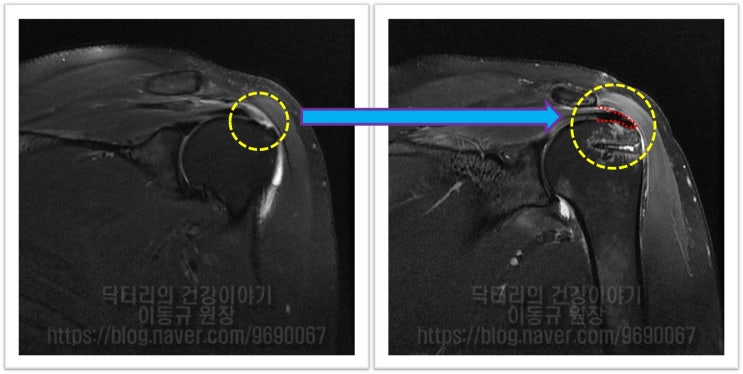

어깨 회전근개 파열 : 보다 단단하게 봉합하는 이열봉합법

안녕하세요. 정형외과 전문의 이동규 입니다. 오늘은 회전근개 파열에서 관절경 수술시 더 단단하게 봉합하...